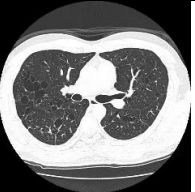

15. 39y/o Female, progressive dyspnea and chest tightness for several days